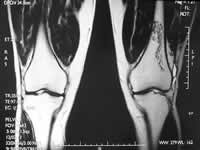

(上图为1列缺血性骨坏死SARS患者的膝关节片。X线平片无异常,MRI显示左侧股骨远端缺血性改变), http://www.100md.com